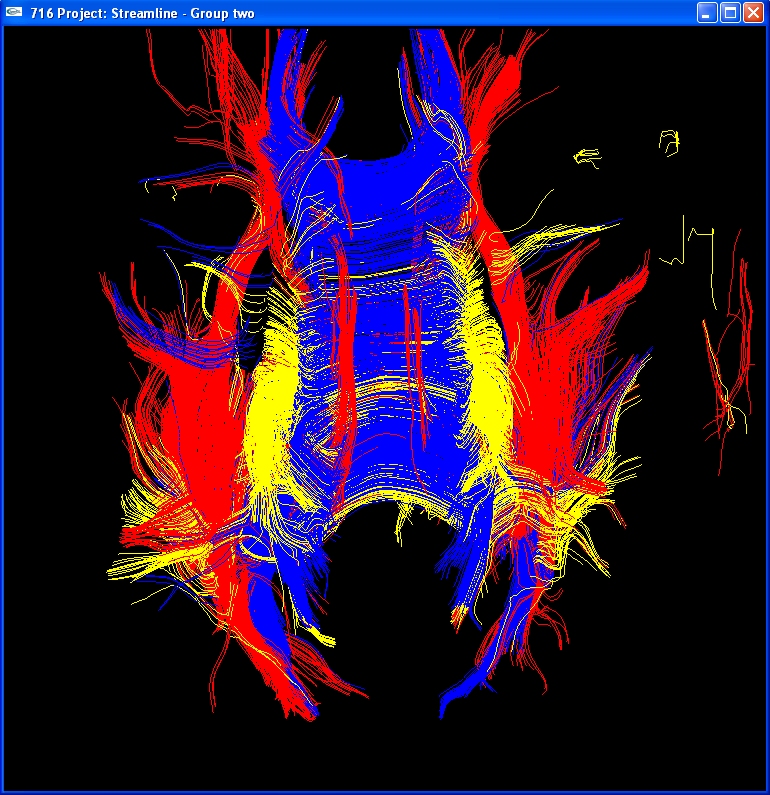

Visualizing Brain Nerve Fibers using Streamlines

2004-10-15, Bo Li, Jing Li, Sharon Liu, Jessica Qu, Fung Yang |